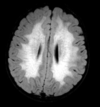

Como a embolia gordurosa se apresenta na imagem?

A

Após 1 dia do trauma grave ou manipulação de medula óssea

Multiplas pequenas lesões em padrão estrelado

Pontinhos pretos (SWI) ou hipersinal no FLAIR